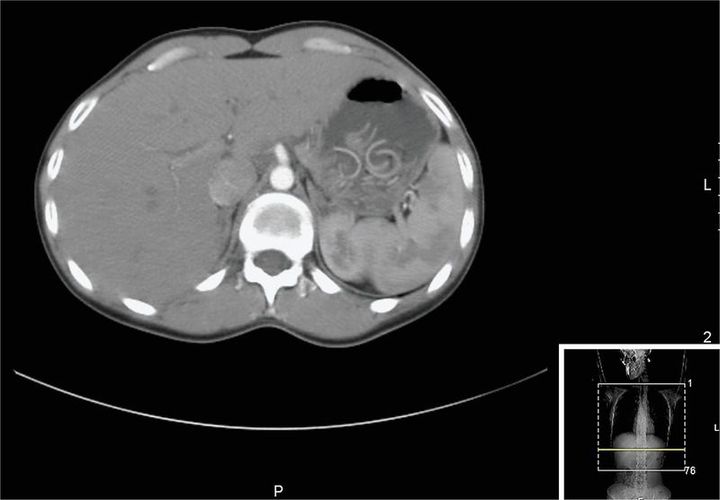

A 30-year-old woman who was otherwise healthy presented to the emergency department with worsening pain in the right upper quadrant that had developed approximately 10 days earlier. She reported that the pain was not radiating but that it was exacerbated by deep inspiration. A review of systems was notable for an irritating cough, decreased appetite, and generalized fatigue. The patient reported that she did not have any other symptoms. On physical examination, she was found to have diminished breath sounds over the right lung field and abdominal pain on palpation of the right upper quadrant. The results of routine blood testing were unremarkable. Axial images of the thorax (shown) and abdomen on a computed tomographic scan showed a distended stomach with worms present; three hypodense nodular formations of the liver were also evident, a finding consistent with biliary cysts. The patient was treated with mebendazole and passed Ascaris lumbricoides worms in her stool. On evaluation 2 months later, she was asymptomatic, and her stool tested negative for parasites. Patients infected with ascaris are often asymptomatic. When patients do present for evaluation, common signs of infection include cough, fever, abdominal discomfort, and eosinophilia. However, as was the case with this patient, the presentation may not follow this pattern, and the diagnosis may be made with imaging.